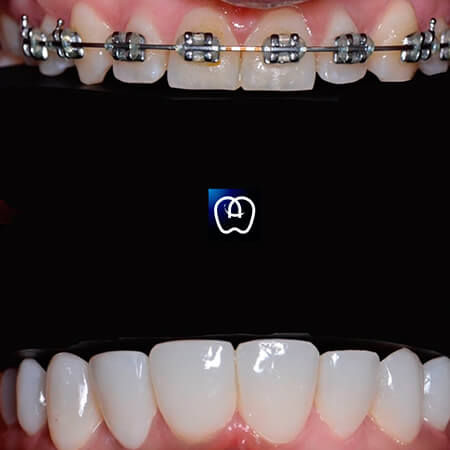

Galería de antes y después

Las especialidades de Álvarez & Arráez Odontología son: Odontólogo, Implantes dentales, Odontología láser, Odontología estética, Rehabilitación oral, Periodoncia, Endodoncia, Odontopediatra, Ortodoncia.